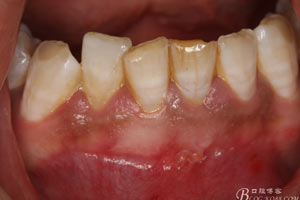

患者、王xx、男、25歲。主訴:下前牙唇側(cè)牙齦溢膿一年?,F(xiàn)病史:患者三年前,下前牙外傷,曾在當(dāng)?shù)鼐驮\,治療經(jīng)過(guò)不詳,近一年,下前牙唇側(cè)反復(fù)溢膿,今來(lái)我院就診。專(zhuān)科檢查:31、41牙冠未變色、31唇側(cè)有一瘺管,捫診溢膿。x光根尖片:31根管已治療。根尖廣泛陰影,波及41牙根的近中面。陰影不規(guī)則。診斷:外傷導(dǎo)致的根尖炎。治療計(jì)劃:31、41行根管治療術(shù)。根管治療術(shù)中發(fā)現(xiàn)31在根尖1/3處出現(xiàn)外吸收,導(dǎo)致根充物外溢。于是在根管治療完畢后,接著行根管外科治療。整個(gè)治療過(guò)程1個(gè)伴小時(shí)。

1.患者術(shù)前的口內(nèi)照片:31唇側(cè)有一膿瘺。捫診溢膿。